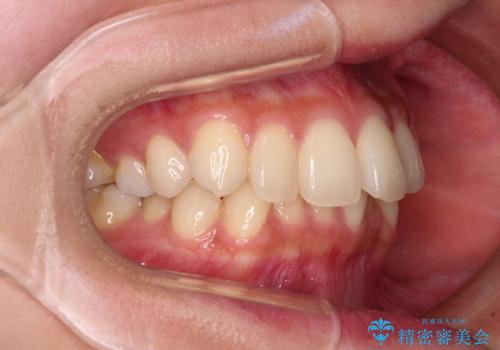

- 前歯のデコボコと強い咬みしめを気にして来院された患者様です。

インビザラインを用いて、前歯の叢生を解消するとともに、ディープバイトを改善していくこととしました。

海外へ転居する予定があったため、1日22時間以上の装着時間をしっかりと守っていただき、予定期間よりも早く、思っていた以上にきれいに仕上げることができました。